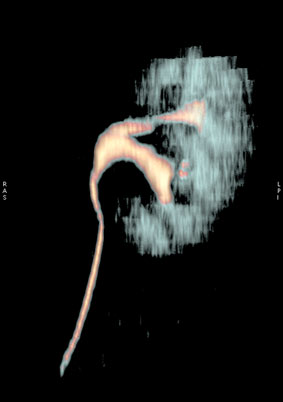

Сонограмма левой почки

1web.jpg (16.33 КБ) 1220 просмотров